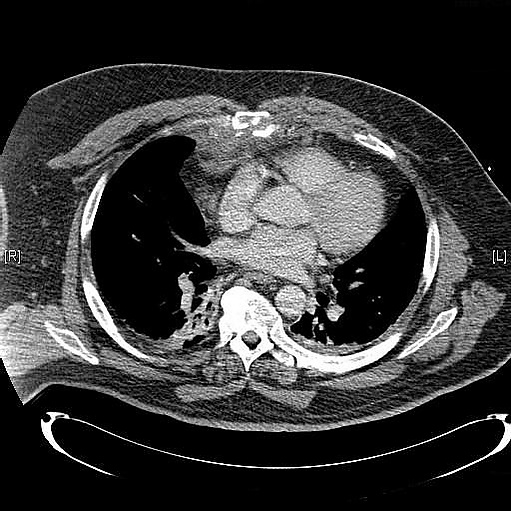

Диагностика

Выполняют рентгенографию грудной клетки в боковой проекции для подтверждения диагноза.